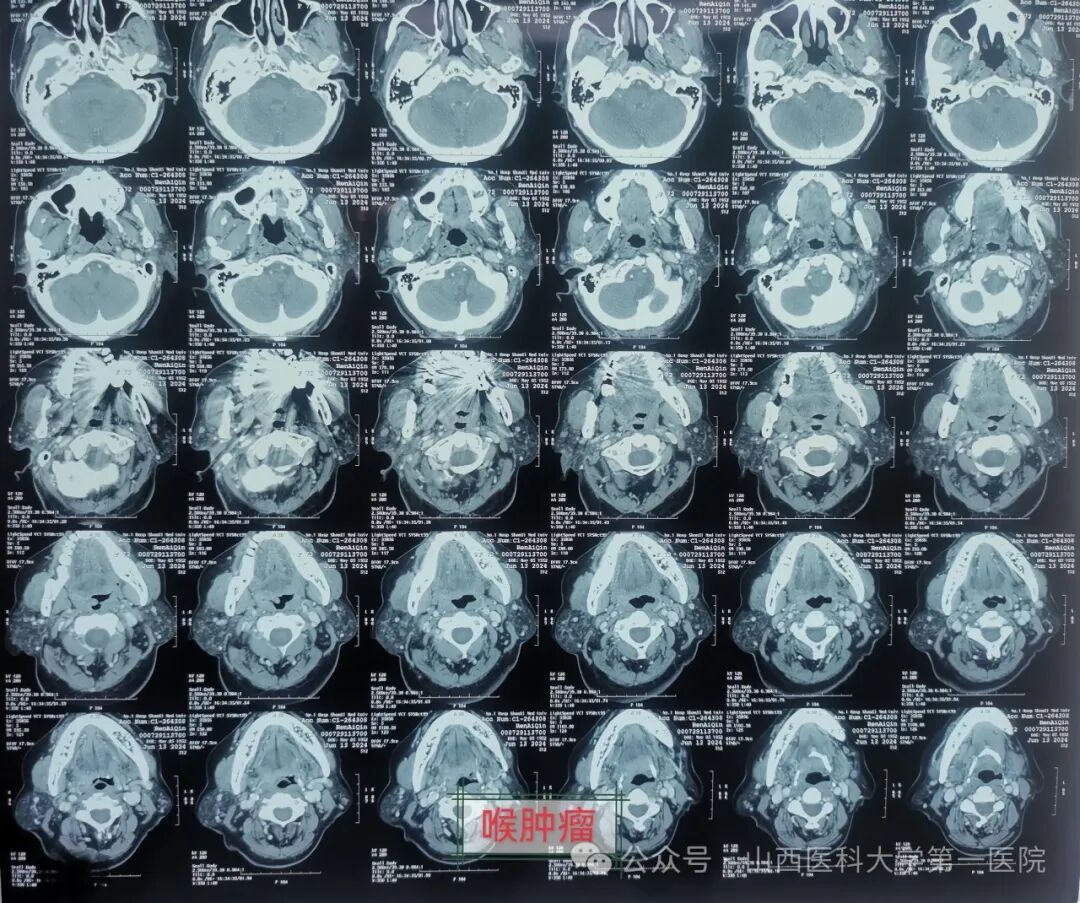

一名来自山西晋中的72岁女性患者数年前由于声音嘶哑而被确诊为喉癌并于外院行喉癌手术治疗,最近1个月以来,患者发现声音嘶哑进一步加重,伴有呼吸困难,同时合并双侧颈部淋巴结无痛性逐步肿大,为进一步明确诊治,就诊于山西医科大学第一医院耳鼻咽喉-头颈外科,通过电子纤维咽喉镜以及颈部影像学CT与MRI检查,被确诊为喉癌手术后复发,颈部淋巴结转移,收入院治疗。

入院后完善各项化验及辅助检查,对患者瘤体血供有了全面了解,同时发现该患者患有高血压等基础疾病史,常年服用降压药物等,经过心血管内科、重症医学科及麻醉科等多学科大会诊和术前讨论,制定出周密的手术方案。